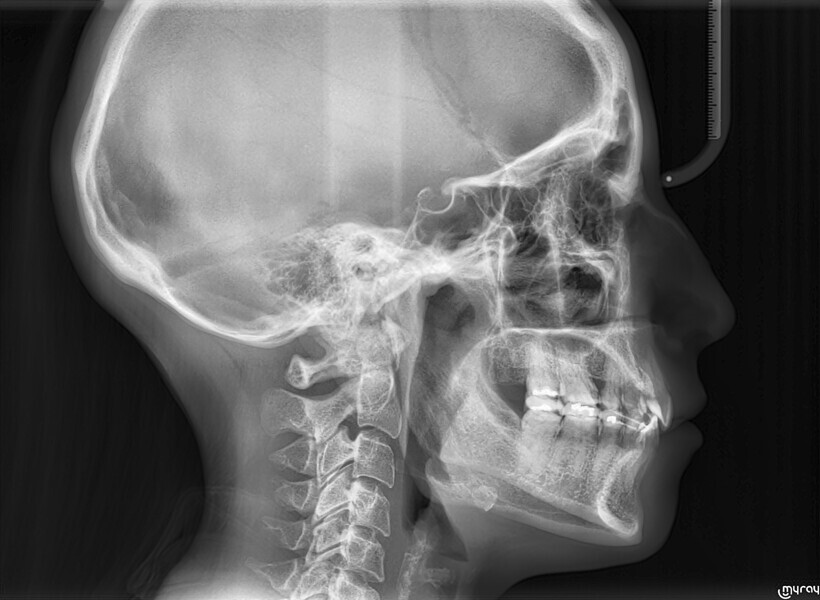

A 35-year-old female patient presented with crowding, muscle and joint pain, and headaches upon awakening. Examination found a skeletal Class I with crowding and bimaxillary protrusion. Facial examination showed a convex profile with protruded lips and a square face shape, intensified on smiling (Figs. 1–4). She reported bruxism, and bilateral masseteric hypertrophy was observed, but there was no alteration of the temporomandibular joints.

Before the aligner treatment began, the maxillary and mandibular second premolars were extracted to create space. With orthodontic treatment, distalisation of the anterior teeth was achieved by employing maximum mandibular anchorage and moderate maxillary anchorage (Figs. 5–7). At the end of the treatment, a stable bilateral Class I occlusion had been achieved, as well as normal inclination and retrusion of the anterior teeth, consequently improving the profile (Figs. 8–10).